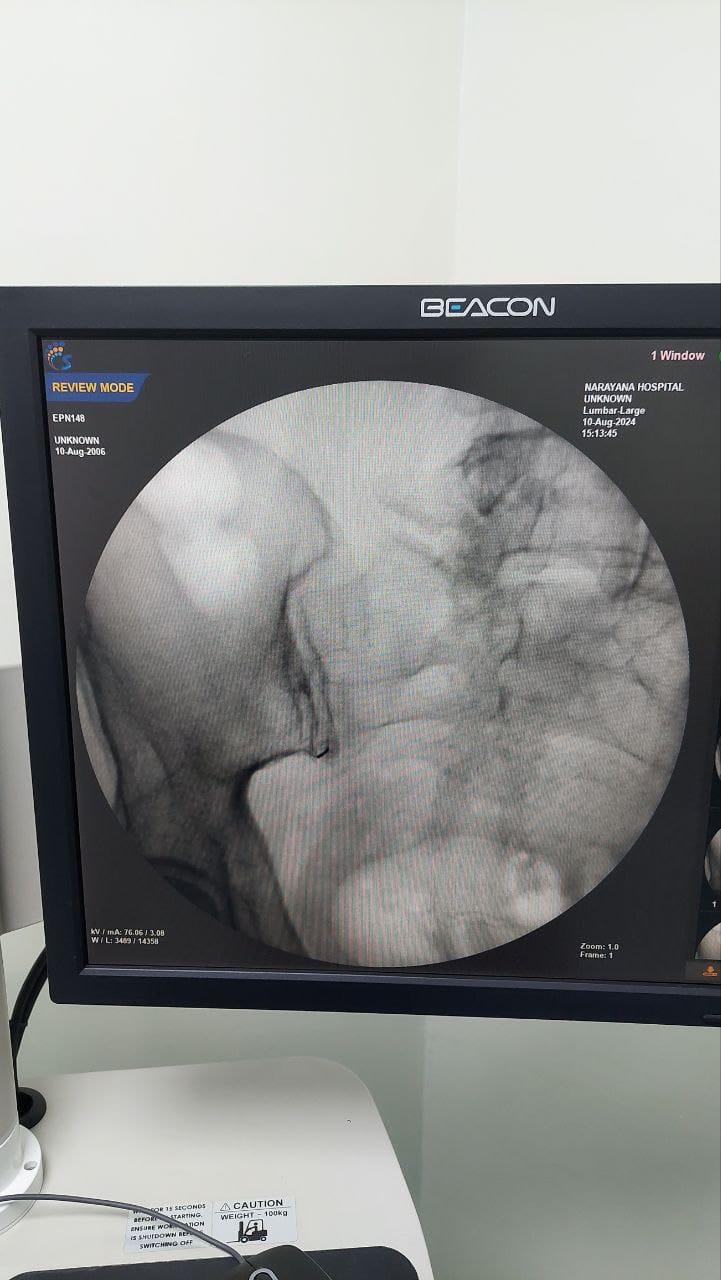

Procedures